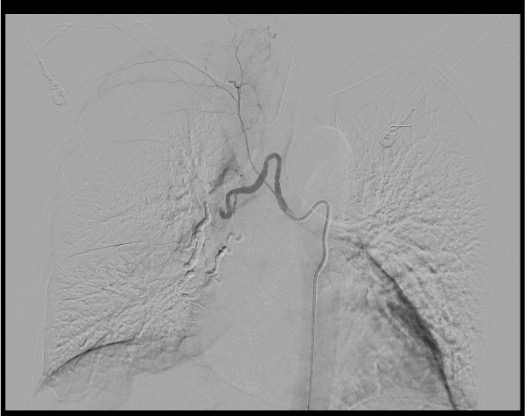

Descending Thoracic Aortogram

Selective Bronchial Artery Catheterization

Angiographic Assessment

T5–T6 Aortic Level

- Primary origin of ~70% of bronchial arteries

- Center your aortogram here

- Corresponds roughly to the carina / left mainstem bronchus on fluoroscopy

- If no bronchial arteries found at this level, extend search above and below